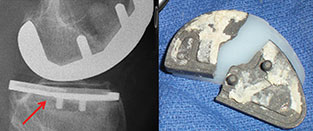

A proposed new ASTM International standard will cover fatigue testing of metallic tibial trays, which are components used in partial knee joint replacement. WK45235, Practice for Cyclic Fatigue Testing of Metal Tibial Tray Components of Unicondylar Knee Joint Replacements, is being developed by Subcommittee F04.22 on Arthroplasty, part of ASTM International Committee F04 on Medical and Surgical Materials and Devices.

Yildirim notes that the testing described in WK45235 mirrors fatigue testing that is currently used for total knee replacement tibial trays. Once the standard has been approved it will be used by medical device companies as well as testing laboratories. The purpose of the test will be to indicate that the tibial metal component will not fail over its expected lifetime.